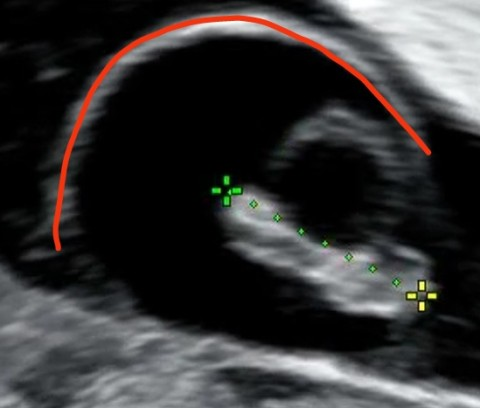

빨간색으로 표시된 흰선은 양막낭(amniotic-sac)입니다. 양막낭은 정상 구조이며, 심장박동수는 직접 초음파를 본것이 아니라 어떤 상태인지 글로는 알기 어렵습니다. 다만 아직 주수가 어려서 정확히 안잡혔을 가능성 있겠습니다.